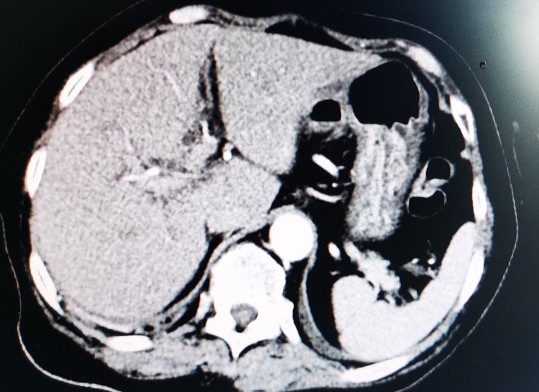

肝脏

正常肝脏CT片

黄婶的肝脏,左右分明,左右肝均萎缩,脾大

萎缩的右肝发展成了肝癌

肝癌向下生长